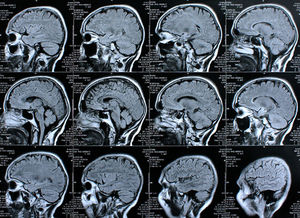

Gehirn-Scans: neuer Behandlungsansatz in Arbeit (Foto: pixelio.de, Rike) |